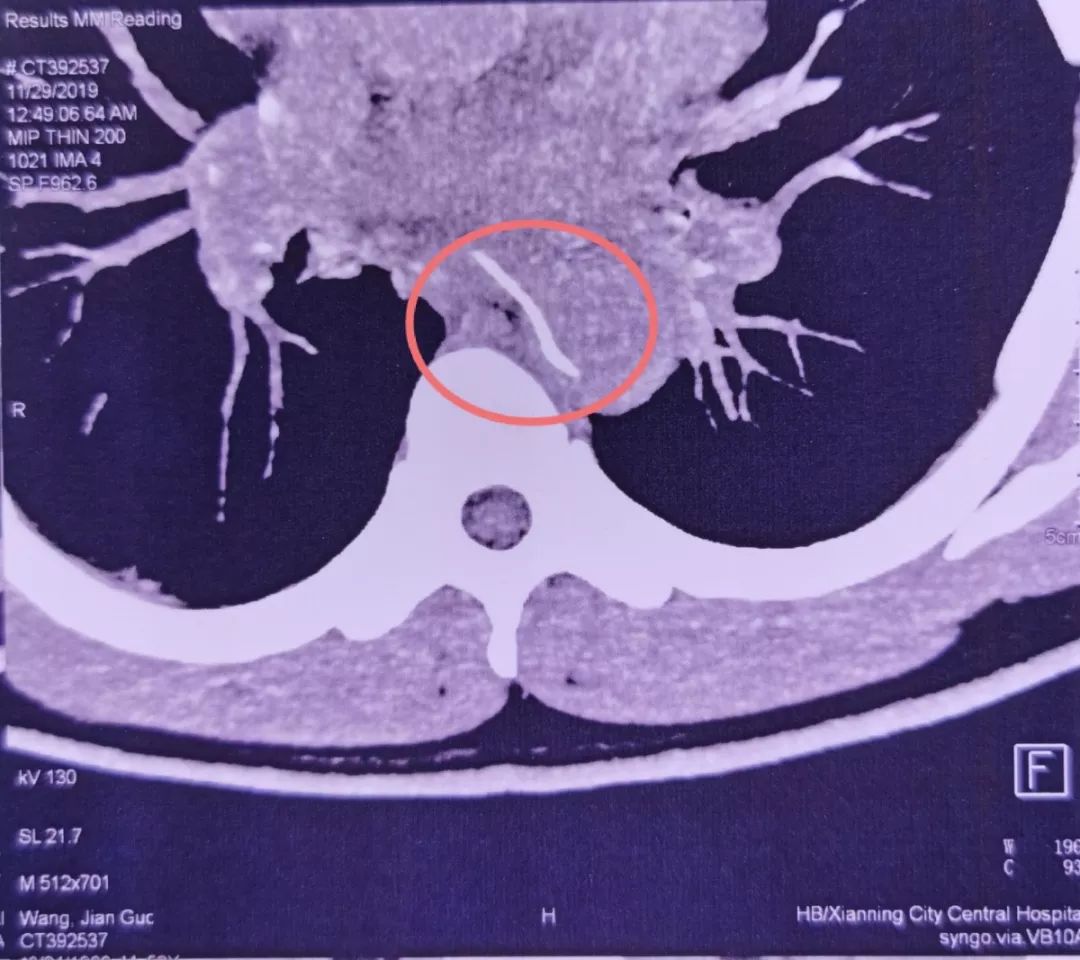

没想到过了两天,他突然感到剧烈胸痛。CTA检查发现,一根鱼刺样的异物卡在了食管内,且已刺穿食管壁,一头扎进了胸主动脉。

后来林先生来到了武汉大学人民医院急诊科就诊。检查发现,鱼刺像一把圆月弯刀,横插在食管和胸主动脉附近。如果盲目拔出,必定会形成主动脉破口,发生大出血。